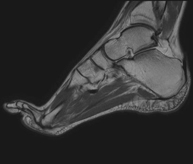

Exploración para el estudio de la articulación y sus frecuentes lesiones de ligamentos (esguinces) así como de la afectación de otras estructuras como el cartílago o el hueso. También es de gran utilidad para diagnosticar alteraciones en el tendón de Aquiles (tendinitis, roturas). Duración de aproximadamente 20 minutos. No emplea radiación ionizante. - RM Pie

Exploración para el estudio de lesiones en tendones músculos y pequeñas articulaciones. Permite valorar con eficacia las lesiones en el cartílago. También es de mucha utilidad para completar la exploración ecográfica previa. No emplea radiación ionizante. Tiene una duración aproximada de 20 minutos. - Artro-RM Hombro